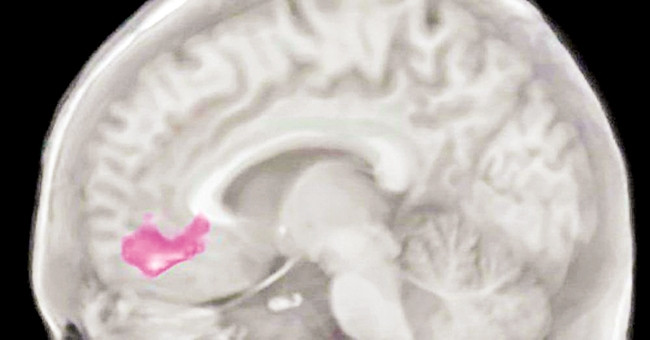

Ở sâu trong thùy trán của não người có một phần tinh vi, phức tạp, đóng một vai trò nghe có vẻ mù mờ nhưng hết sức quan trọng: tham gia điều chỉnh nhận thức và cảm xúc. Nó có một cái tên dài dòng - ventromedial prefrontal cortex - ta cứ gọi tắt là VMPC.

Ở người bình thường, mỗi khi sắp ra một quyết định, VMPC sẽ kết nối với các vùng não khác để cùng nâng lên đặt xuống, nghĩ đến hậu quả về mặt đạo đức, đến những thứ cần ưu tiên rồi mới quyết. Trên thí nghiệm, các nhà khoa học thấy, khi nghĩ đến những quyết định “đạo đức” (thí dụ có nên nói dối không), VMPC sẽ tăng hoạt, còn khi ra các quyết định “vô hại” (thí dụ nên ăn gì bây giờ), VMPC sẽ không tăng hoạt.

Trái lại, tổn thương vùng VMPC (do chấn thương, do dùng ma túy, v.v.) khiến nó không kết nối được các vùng não khác, dẫn đến lệch lạc về xử thế. Bệnh nhân có thể vẫn ăn uống, đi lại bình thường nhưng sẽ hành xử lạnh lùng, ích kỷ do khi ra các quyết định có liên quan đến đạo đức, có liên quan tới người khác thì vùng VMPC của họ đã “hỏng”.

Christina Karns bảo, hãy tưởng tượng vùng vỏ não VMPC chính là quầy đổi tiền để ta đổi từ đô-la sang bảng Anh và ngược lại. Ở người bình thường, quầy VMPC quy tỷ giá của những việc làm “cho người khác” là cao hơn những việc “cho bản thân”. Theo “tỷ giá” này, mỗi khi ta có một quyết định “vì người khác”, VMPC và cộng sự của nó sẽ lao vào tính toán, rồi trả cho ta một loại “tiền thưởng” của hệ thần kinh, tức các chất dẫn truyền thần kinh khiến ta hài lòng, thỏa mãn.

Để chứng minh điều này, đầu tiên Christina Karns và cộng sự chọn ra hai nhóm người, trong đó có một nhóm tốt bụng hơn. Tiếp đó, cô mời từng người trong hai nhóm chọn “cho” hay “nhận” để máy tính theo đó chuyển một số tiền thực vào tài khoản của bếp ăn từ thiện hay vào tài khoản của chính họ. Theo dõi trên máy scan MRI, Christina thấy, vùng não VMPC của những người tốt bụng hơn sẽ có đáp ứng mạnh hơn khi thấy tiền được chuyển vào bếp ăn từ thiện: quầy đổi tiền VMPC đã chi trả đậm “tiền vui” cho những người này.

Quay lại với Christina Karns, cô chia tiếp những người tham gia thí nghiệm ra làm hai nhóm. Một nhóm trong ba tuần liền chỉ viết nhật ký về những điều họ biết ơn. Nhóm còn lại thì viết về đủ các chủ đề khác, ngoại trừ biết ơn. Kết quả, những người chỉ viết về biết ơn sau đó thấy mình sống tình cảm hơn, thích giúp đỡ người khác hơn, và các mối quan hệ của họ cũng tốt hơn. Quan trọng nhất, quan sát qua máy scan MRI, Christina thấy vùng VMPC của những người sau ba tuần chỉ viết về biết ơn càng đáp ứng mạnh hơn nữa khi chứng kiến tiền được đổ vào bếp ăn từ thiện!